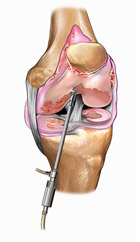

Con l’avvento negli anni ’80 dell’artroscopia (procedura chirurgica mininvasiva che, attraverso l’utilizzo di minitelecamere a fibre ottiche e di strumentari dedicati, permette l’accesso a una articolazione senza aprirla), la chirurgia soprattutto del ginocchio e della spalla si sono radicalmente evolute. Dopo qualche decennio di applicazione ed evoluzione tecnologica, attualmente quasi tutte le articolazioni più importanti possono essere aggredite artroscopicamente. Ciò ha reso possibile il trattamento di innumerevoli lesioni con traumi chirurgici molto ridotti favorendo i processi di guarigione e il recupero funzionale.

La tecnica chirurgica prevede la preparazione di 2 tunnel ossei (tibiale e femorale) entro cui viene fatto passare il trapianto debitamente preparato che verrà poi fissato con viti o pin (metallici o di materiale riassorbibile).